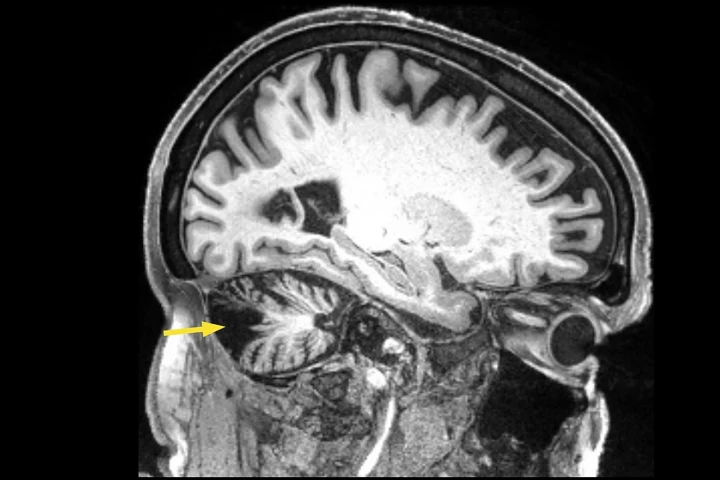

Researchers used repetitive magnetic stimulation on the brain of a man who’d had a stroke 12 years ago, improving his walking speed, balance, and coordination. The innovative treatment offers hope to others affected by stroke, even years after.